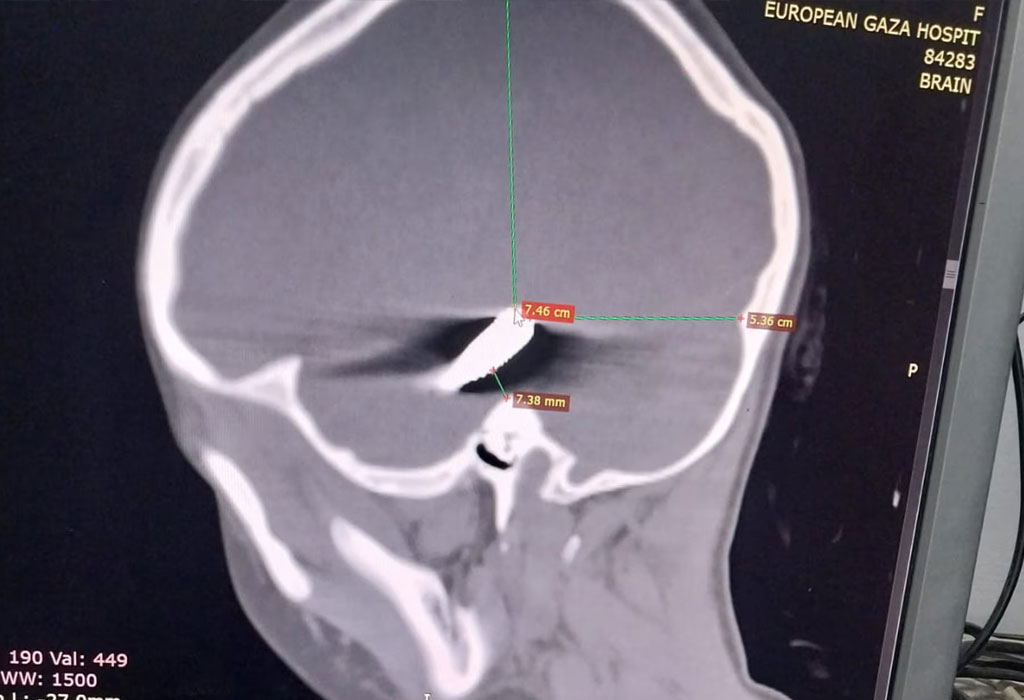

“Bila je još jedna mala djevojčica otprilike iste dobi. Vidjela sam ulaznu ranu od metka na njenoj glavi. Njen otac je bio tamo, plakao je i pitao me, ‘Možete li je spasiti? Ona je moje jedino dijete.'” Gupta je rekla da je i treće malo dijete također imalo pogodak u glavu i poslano je na CT snimanje.

“Neurokirurg je pogledao i rekao: ‘Nema nade.’ Mogli ste vidjeti da je metak prošao kroz glavu. Ne znam koliko je bio star, ali je mlad,” rekla je. Članovi obitelji rekli su Gupti da se izraelska vojska povukla s područja udaljenog oko četiri kilometra od bolnice.

Gupta je Guardianu dostavila CT snimke djece s ranama na glavi. To je uključivalo osmogodišnju djevojčicu za koju je patolog opisao da pokazuje “ranu od metka u glavu koja ulazi s desne strane s metkom u mozgu (medijalni desni temporalni režanj)”.